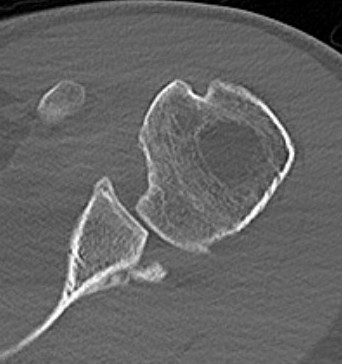

CT

Hill Sachs lesion / posterior bony bankart / glenoid retroversion

Reverse Hill Sachs / Posterior bony Bankart / Glenoid retroversion